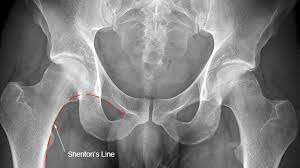

X-rayPelvis both hip

X-ray hip joint